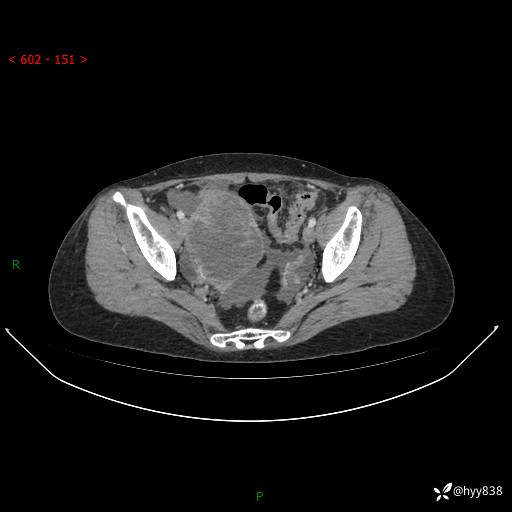

腹盆CT平扫

增强